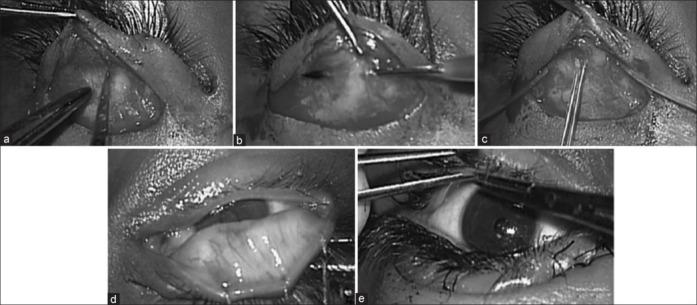

硅胶吊带手术治疗先天性上睑下垂:跗骨管技术。

Silicone sling surgery for congenital ptosis: Tarsal tunnel technique.

This was a prospective, interventional, comparative study conducted on patients with congenital simple severe ptosis. A novel method of silicone rod fixation to the tarsus (tarsal tunnel technique, group 1) was done compared with a conventional technique of silicone rod fixation (suture fixation technique, group 2) in frontalis suspension surgery. A total of 30 patients were randomized into two groups of 15 patients each. Postoperatively, MRD1, vertical palpebral aperture, and eyelid fold height were comparable in both groups till the last follow-up with stability in eyelid position. Patient satisfaction scores showed similar results with good-fair satisfaction grading in 13 patients in group 1 and 11 patients in group 2 at 6 months follow-up. No significant complications occurred in either group. Tarsal tunnel fixation of silicone rods is a novel method in sling surgery with optimal cosmetic and function outcomes. Further long-term studies are needed to validate the results of the technique.

摘要